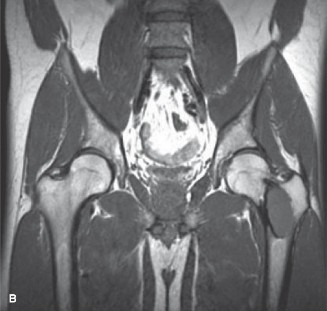

Magnetic Resonance Imaging (MRI) of the Left Femur:

An MRI was obtained to assess marrow involvement, soft tissue extension, and to rule out secondary aneurysmal bone cyst (ABC) or other features suggestive of malignant transformation.

* T1-weighted images: Demonstrated heterogeneous low-to-intermediate signal intensity within the lesion, reflecting its predominant fibrous and immature osseous components.

* T2-weighted images: Showed areas of high signal intensity, consistent with fibrous stroma, areas of fluid, and potentially hemorrhage associated with the fracture. Importantly, no definitive fluid-fluid levels were identified, which would have been highly suggestive of an ABC.

* Post-contrast T1-weighted images with fat saturation: Revealed heterogeneous enhancement, primarily peripheral, with some internal septal enhancement.

Crucially, the MRI did not show overt aggressive soft tissue invasion, extensive peritumoral edema, or solid enhancing nodules typically associated with high-grade sarcomas. There was no evidence of skip lesions within the medullary canal. The findings were largely consistent with fibrous dysplasia, but the expansile nature and subtle soft tissue signal changes necessitated a careful differential diagnosis, particularly from an oncological perspective.